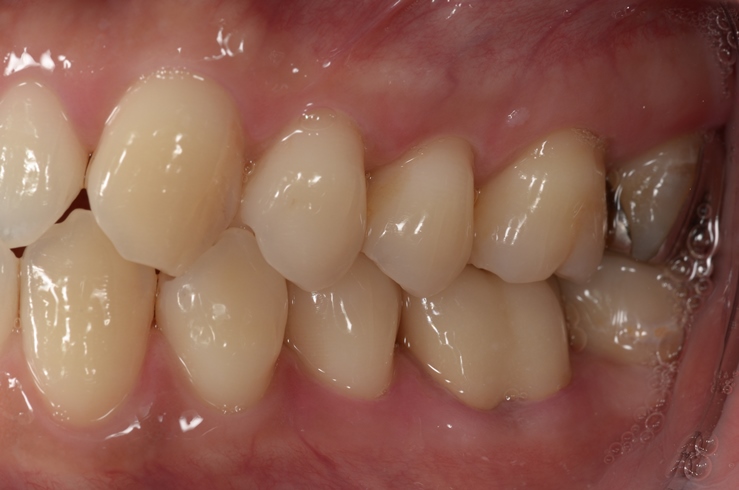

その後は、症状も特になく経過良好であることからかぶせ物を入れて終了となりました(^0^)/

終了時はこんな感じ!